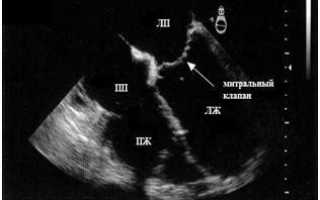

Сердце человека при эхокардиографическом обследовании (УЗИ сердца). Добавочная хорда представлена эхоплотным линейным образованием, которое можно просмотреть в двух плоскостях сечения, расположенным в полости левого желудочка (ЛЖ), ближе к митральному клапану.